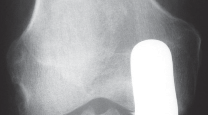

التصوير الطبي ضروري لتأكيد التشخيص وتحديد مدى تلف المفصل:

-

الأشعة السينية العادية (Plain Radiographs):

- المنظر الأمامي الخلفي (AP): يُظهر الركبة من الأمام.

- المنظر الجانبي (Lateral): يُظهر الركبة من الجانب.

- المنظر الخلفي الأمامي المثني (PA Flexed): يسمح بتقييم أفضل للجزء الخلفي من الركبة وقد يكشف عن تغيرات أكبر في الحجرة الخلفية الوحشية.

- منظر شروق الشمس (Sunrise/Patellofemoral): لتقييم المفصل الرضفي الفخذي.

- الأشعة السينية الطويلة للطرف السفلي بالكامل (Full-length standing radiographs): من الورك إلى الكاحل، وهي مفيدة جدًا، خاصة إذا تم استخدام تقنيات الملاحة الحاسوبية. تُظهر هذه الأشعة المحاذاة الكلية للطرف السفلي.